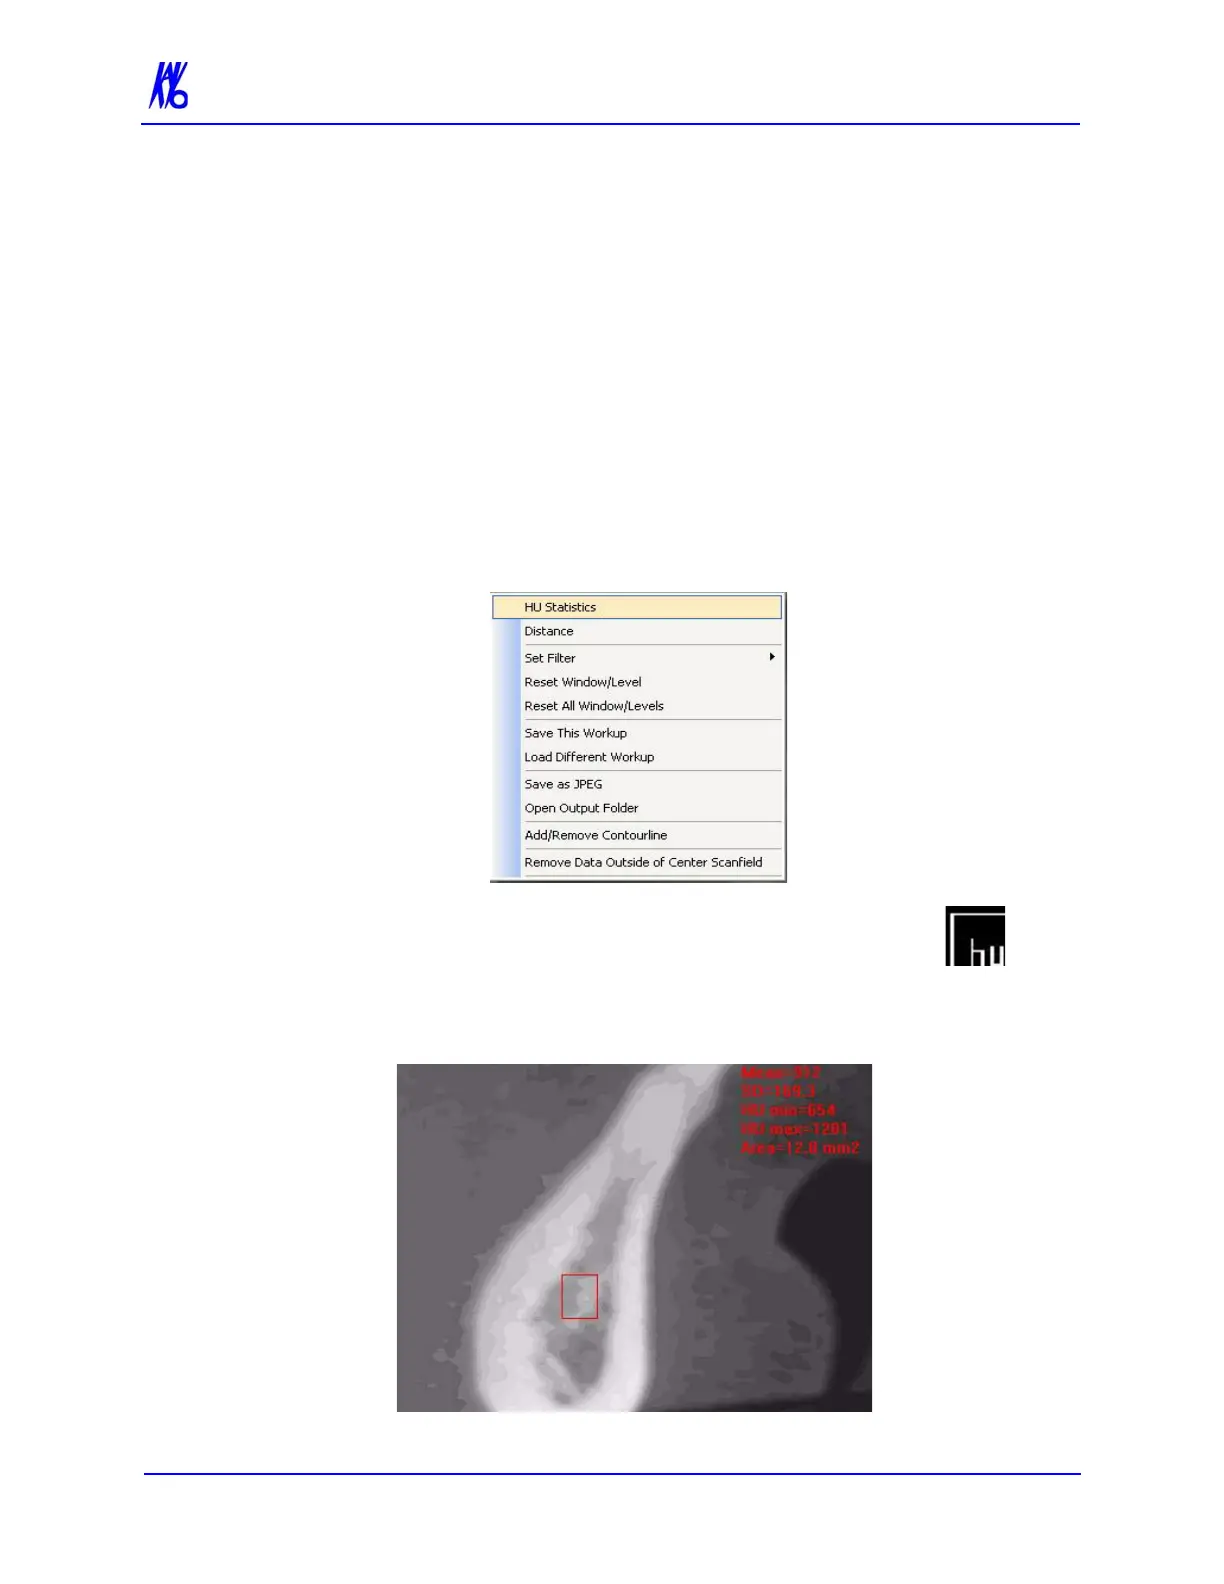

1. To make an HU measurement, right click image and select HU

Statistics.

The menu closes and the cursor changes to the hu

measurement symbol.

2. Click, drag, and click to define an area. Measurement

statistics appear in the upper right corner of the image.